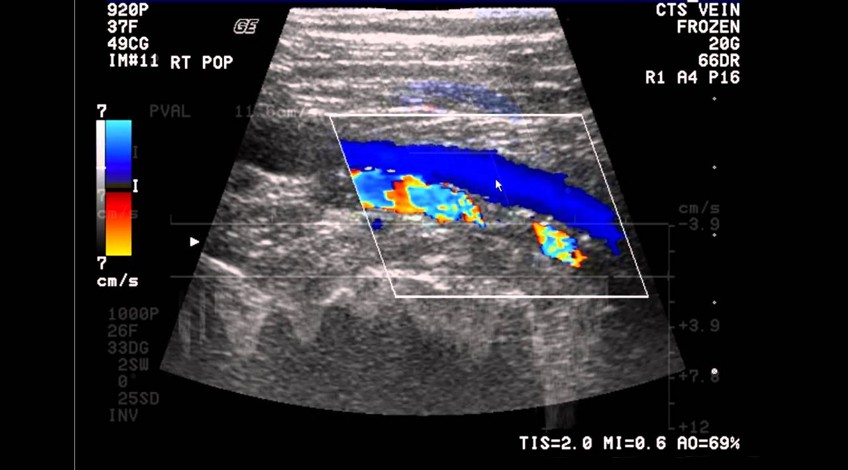

Ecotomografía Doppler

- ¿Qué es? Es un examen que se realiza para estudia el flujo sanguíneo a través de venas y arterias. Se realiza a nivel de piernas, brazos, cuello, abdomen o testículos